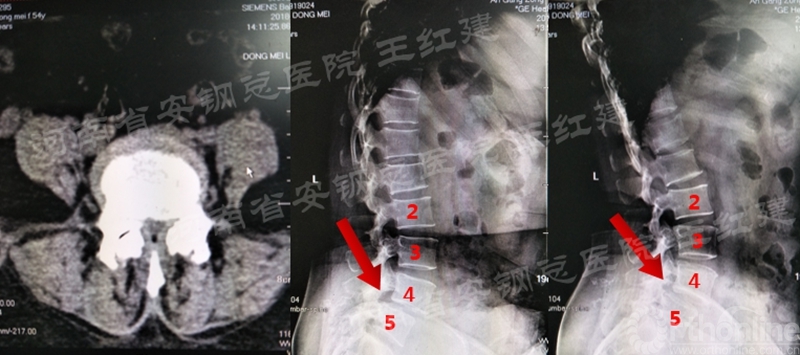

术前

术后

置入内镜通道,用磨钻和枪钳切除上位椎板下缘、下位椎板上缘及突间关节内缘,切除黄韧带,完成单侧入路双侧减压。

应用通道技术进行植入融合时,首先要更换工作套管,通过枪钳、抓钳的应用处理椎间盘,接着进行自体骨或同种异体骨及cage植入,并通过C臂透视确定试模型号放置融合器,最终完成植骨融合。